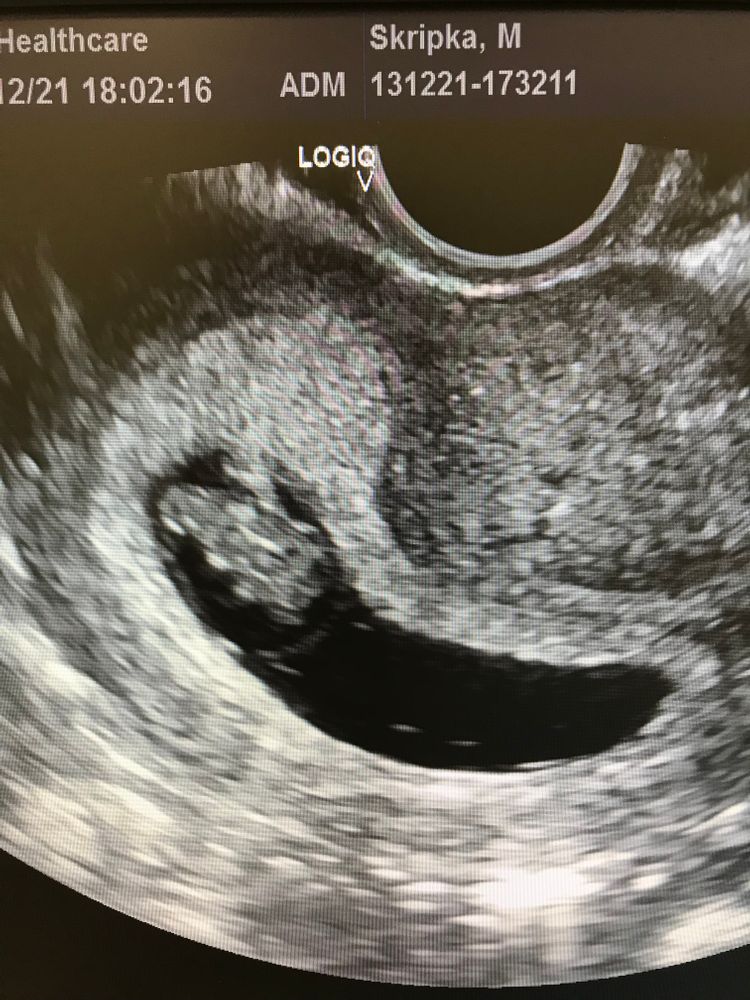

Марго, у меня плодное яйцо сплющено прям, эмбриончик сжат

Всё обязательно получится, у меня тоже вот так было вытянуто в 8 недель, в 6 еще хуже, тоже лежала и пила все, что сказали в жк. Лучше перестраховаться. Потом, ближе к 9 неделе тонус вообще перестал мучить, иногда совсем слегка чувствуется тяжесть, но намного легче, чем было) надеюсь, у вас все обойдется и будет хорошо❤️ Изображение